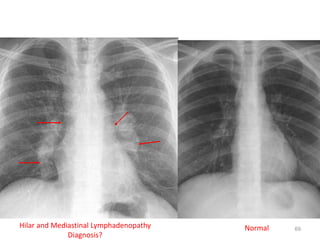

69

154 slides Normal

Hilar and Mediastinal Lymphadenopathy

Diagnosis?